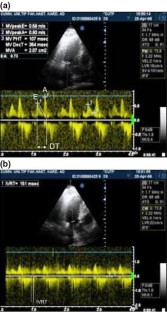

For subjects with tortuosity, early transmitral inflow (E) velocity was lower, late transmitral inflow (A) velocity was higher, E/A ratio was smaller compared with subjects without tortuosity (P < 0.001). Subjects with tortuosity had longer deceleration time of E velocity (DT) and isovolumic relaxation time (IVRT) than did subjects without tortuosity (P < 0.001). End-diastolic interventricular septal and left ventricular posterior wall thicknesses were greater in subjects with tortuosity than those without tortuosity (P = 0.01 and P = 0.005). There was an inverse correlation between total number of arteries with tortuosity and E/A ratio (r = −0.750, P < 0.001). Total number of arteries with tortuosity displayed correlations with DT (r = 0.723, P < 0.001) and IVRT (r = 0.703, P < 0.001).

Fig. 2